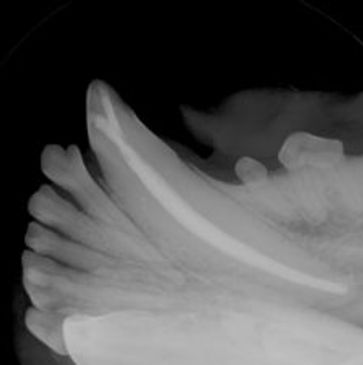

Endodontic therapy is treatment of a diseased exposed pulp cavity. Root Canal and Vital Pulp Therapy can be performed to treat and save fractured or non-vital teeth.